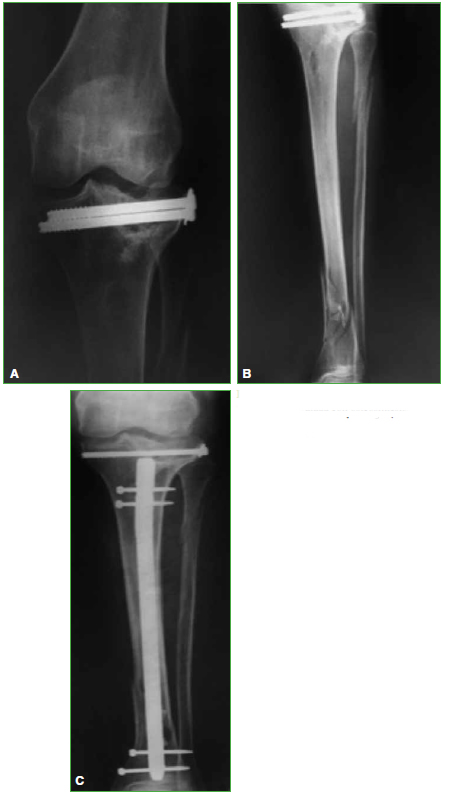

aterials and Methods: We carried out an observational, retrospective study on TKA patients treated between May 1999 and January 2013. We evaluated 25 TKAs, performed on 24 patients, with knee fracture sequela, with an average follow-up of 6.1 years and an average age of 67.1 years. Three cases (12%) had required additional surgeries before TKA. Eight cases (32%) were 2-stage surgeries. Constrained implants were used in four cases (16%). The Knee Society Score (KSS), the Functional KSS (KSSf) and the Range of Motion (ROM) were evaluated preoperatively and at the last follow-up. Prosthesis survival evaluation was documented.

Results: KSS increased from a preoperative average of 38.5 to a postoperative average of 82.8. Postoperative KSSf increased on average from 48 to 85. ROM increased on average from 7.5°-76° to 1°-102.4°. Four patients required a second surgical procedure. Prosthesis survival was 92% at a 6.1-year average follow-up.

Conclusion: TKA is an appropriate treatment for advanced PTOA, with good mid-term outcomes. If adequate postoperative alignment and correct component positioning is achieved, expected outcomes are satisfactory and similar to those with TKA in primary osteoarthritis.